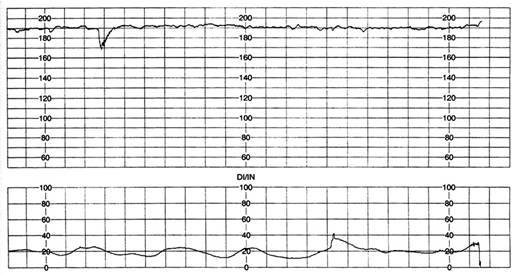

Fig. nr.292 RCFB normal

Inainte de 32 saptamani, de obicei fetii sunt cu RCFB usor mai crescut, apoi RCFB este intre 120 - 160 bpm,( se accepta si 110 - 150 bpm ) ca dupa 42 saptamani sa scada la 100 - 110 bpm.

Fig . nr. 293 Exemplu de masurare a variabilitatii RCF , intre doua linii,trecerea din starea de somn linistit, in cea de somn activ